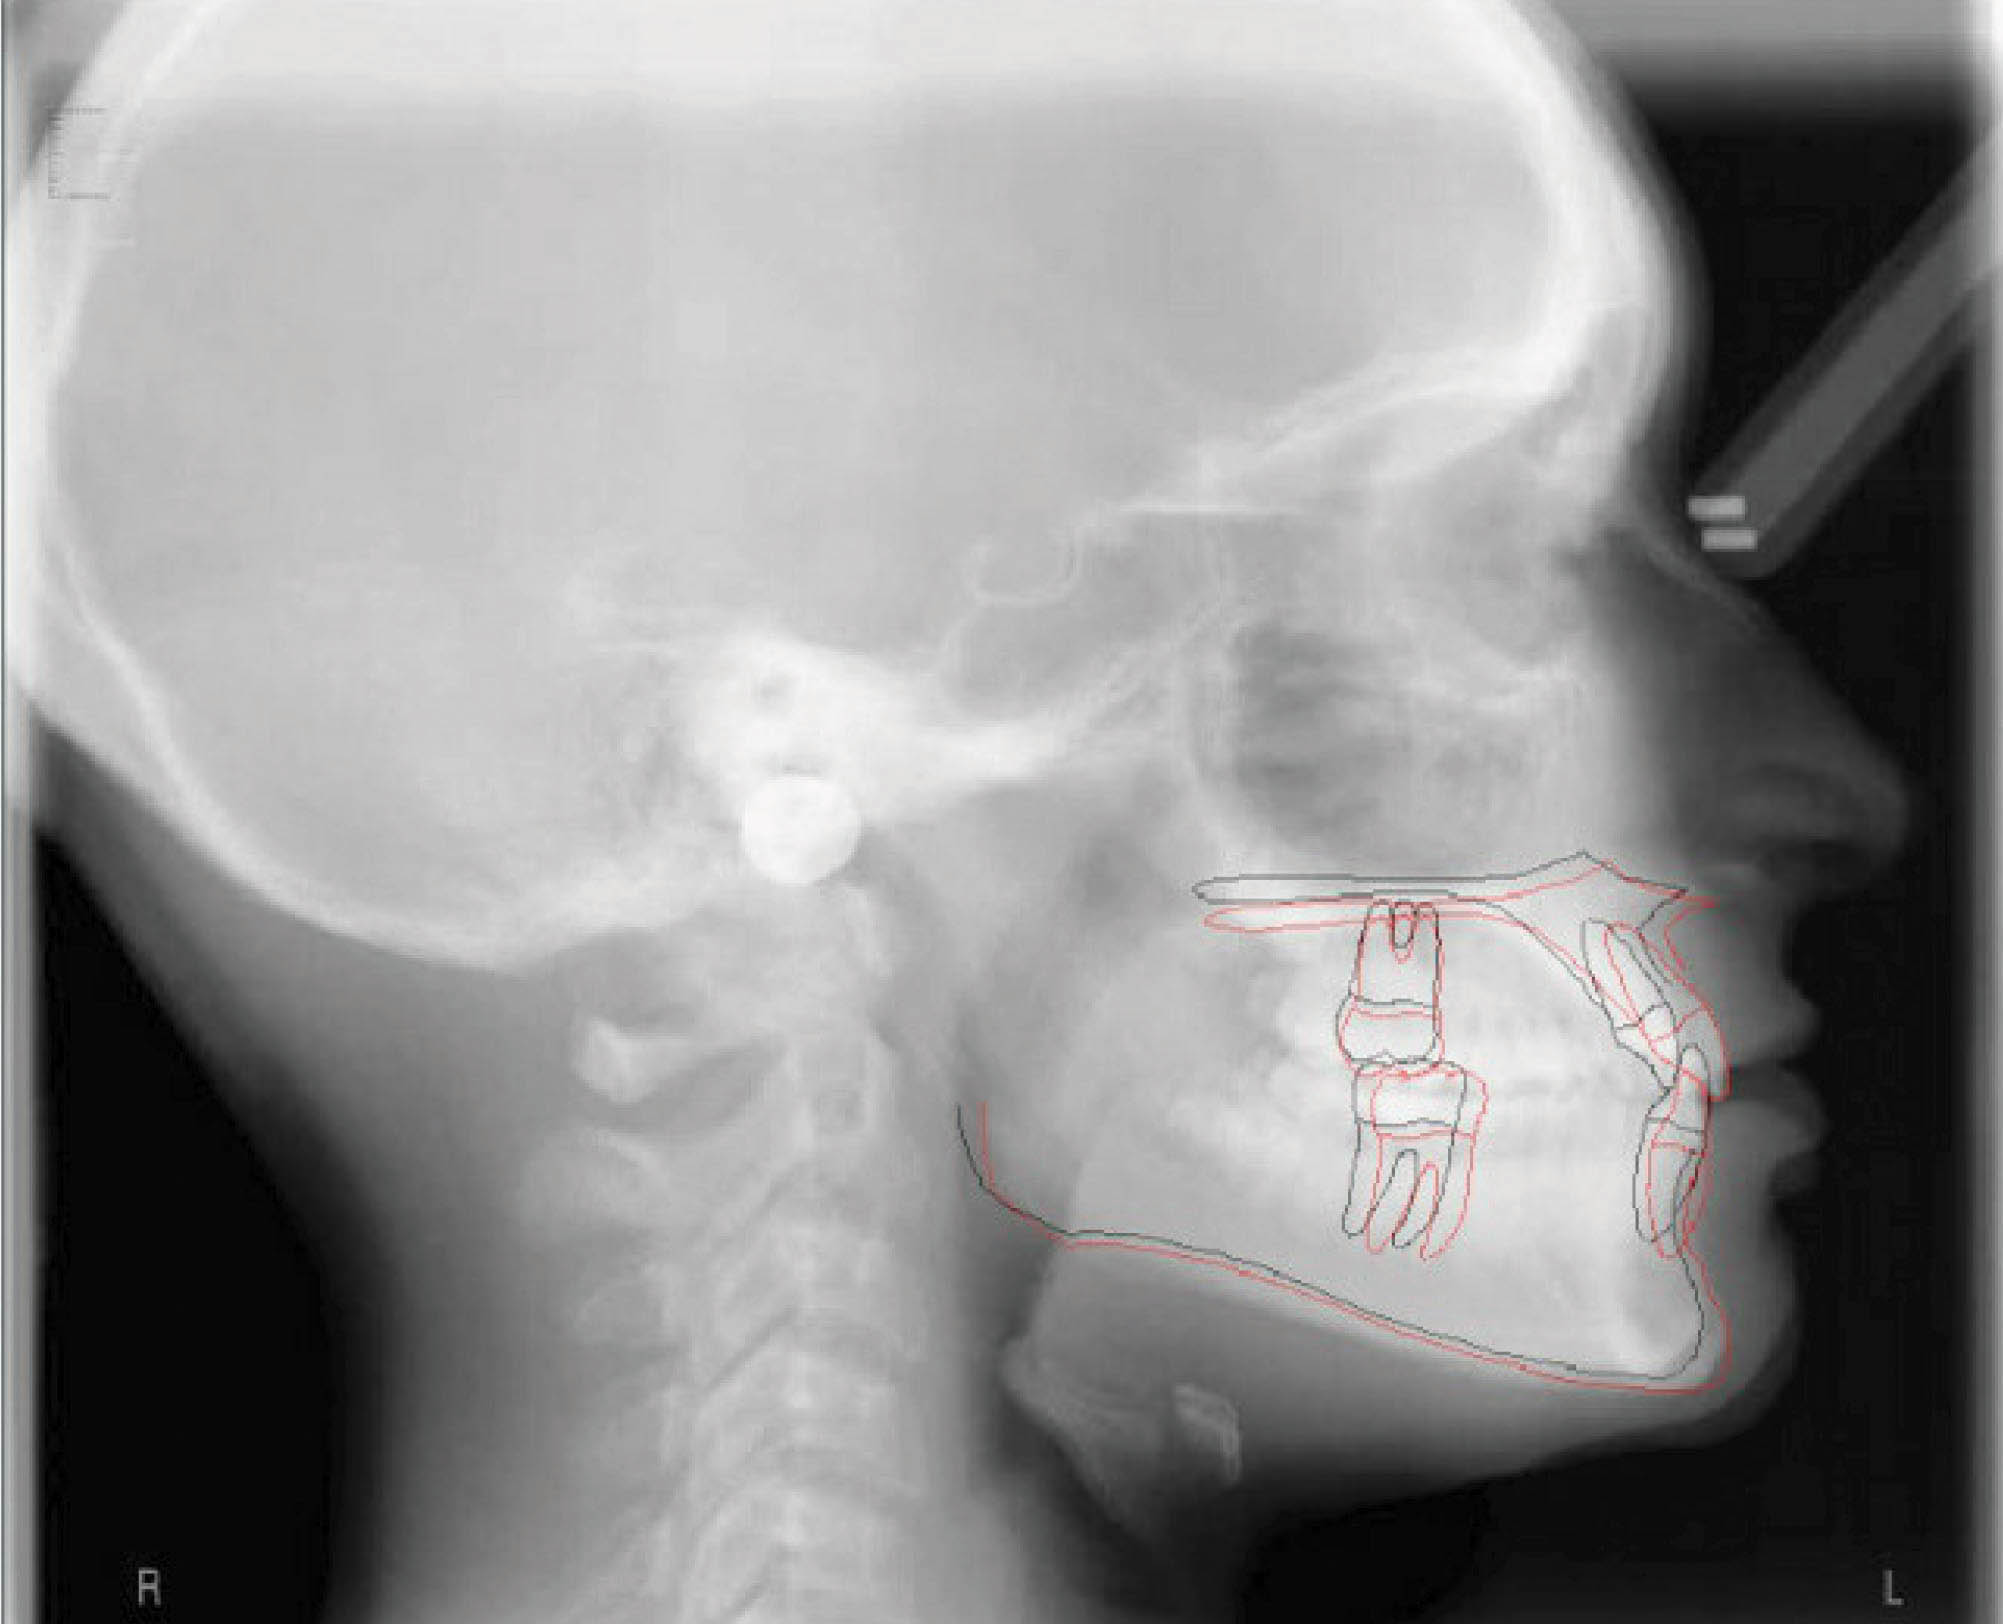

بیمار بعدی دختر ۱۲ ساله در مرحله اواخر میکس دنتیشن (شکلهای 92-۶ الی 94-۶) با اکلوژن ClII/1 است، دیپ بایت و کرادینگ دو فک دارد و لینگوالی شدن دندانهای قدامی بالا و پایین مشخص است. در (شکل 92-۶) هر دو لترال پایین را مشاهده میکنید که بلاک شدهاند. در OPG چیز خاصی مشاهده نمیشود و در لترال سفالومتری ارتفاع عمودی صورت کمی کاهش یافته و انسیزورها رترود شدهاند.

شکل 92-6

شکل 93-6

شکل 94-6

در انتهای درمان هم کرادینگ خوب درمان شد و هم رابطه مولری درست گردید (شکلهای 95-۶ الی 97-۶). عکس OPG طبیعی و سوپرایمپوز نمودن عکسهای لترال سفالومتری نشاندهنده پروترود شدن انسیزورهای بالا و پایین میباشد.

نکته: همانطور که در مقالات در اول مبحث بیان شد، موقعیت مولر بالا و نقطه A در طول درمان فرقی نمیکند. این تغییرات مانند استفاده از هدگیر است در حالیکه با الاستیک کلاسII بدست آوردهایم. ضمناً رشد مندیبل و قدامیتر قرار گرفتن نقطه پوگونیون هم مشخص میباشد و منجر به کاهش تحدب صورت گردیده است.

نتیجه: طول درمان ۲۸ ماه با دو قالبگیری مجدد و الاستیک کلاسII ۲ انسی بود.